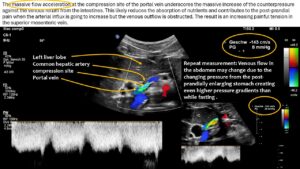

Since the common hepatic artery compressed the portal vein significantly with a flow acceleration to 147 cm/s the pressure within the splenic vein was completely transferred onto the venous return from the small bowel via the superior mesentric vein.

- Severe compression of the portal vein by the common hepatic artery reducing the venous outflow from the small intestines and thus contributes to the maldigestion and malabsorption of the patient

The superior mesenteric vein and the splenic vein converge to form the portal vein. This vessel is typically of a relatively short length, given that the confluence of the superior mesenteric and splenic veins occurs in close proximity to the liver in most individuals. However, in this particular case, the portal vein exhibited a notable elongation, a consequence of the left-sided unification of the superior mesenteric and splenic veins. This anatomical variation potentially renders the portal vein more vulnerable to dislocation, making subsequent compression by the common hepatic artery easier. It should be noted that similar cases have been previously documented on this website, albeit in the absence of malrotation. In these cases, the compression was precisely at the point of unification between the two veins, namely the superior mesenteric and splenic veins. This may have resulted in a residual bypass from the superior mesenteric vein to the portal vein, thereby leading to a subtotal compression of the superior mesenteric vein.

All In this instance, the circumstances were somewhat divergent. The portal vein was of a greater length due to the unification of the splenic and superior mesenteric veins being in close proximity to the spleen. Consequently, there was a complete transfer of pressure from the compression site at the portal vein to both of these veins.

This showed that blood flow to the small bowel was reduced, probably because of the blockage. Moreover, this situation implies increased pressure in the superior mesenteric vein which was much wider than the accompanying superior mesenteric artery as a sign of the painful distension. An increase in intra-abdominal pressure, whether it occurs orally or via a feeding tube, can result in the onset of acute pain due to the subsequent rise in pressure within the mesenteric and renal veins on the left side of the body. This phenomenon is further compounded by the obstruction of venous outflow from the spleen, which can exacerbate discomfort in the region below the left rib cage.